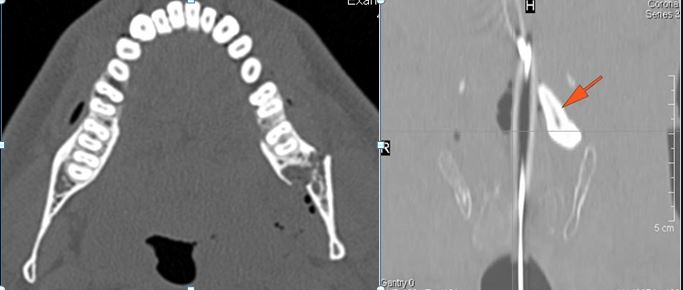

There is bony injury or displacement of the body, angle, ramus, parasymphyseal region, alveolar ridge, and condylar and coronoid process of the mandible. [In case of fracture, describe complexity and displacement]. [Yes/No]

There are dental fractures and/or missing or displaced teeth. [Yes/No]

There is bony injury of the body, alveolar ridge, premaxilla, the infraorbital rim, the palatine or the frontal process of the maxillary bones on either side. [Yes/No]